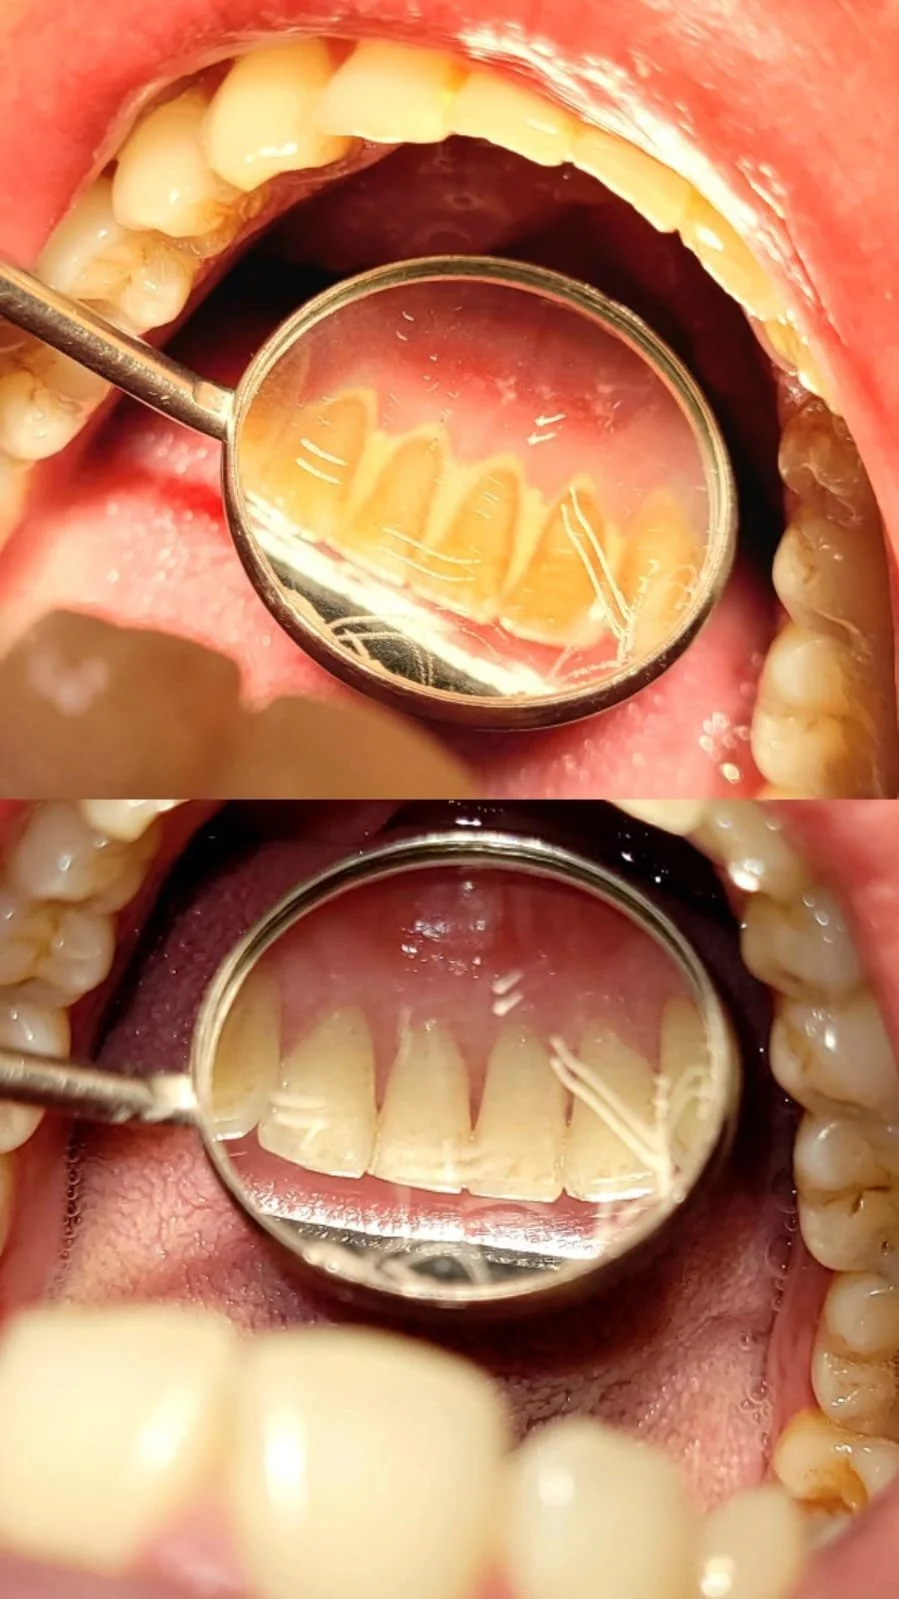

Limpieza Dental Profesional

La limpieza dental es un procedimiento fundamental para mantener una buena salud oral. Consiste en la eliminación del sarro acumulado y de las tinciones provocadas por hábitos cotidianos como el consumo de café, té o tabaco.

Se recomienda realizarla cada 6 meses, ya que además de limpiar en profundidad, permite realizar una evaluación integral para detectar de forma temprana posibles lesiones de caries u otras afecciones dentales.